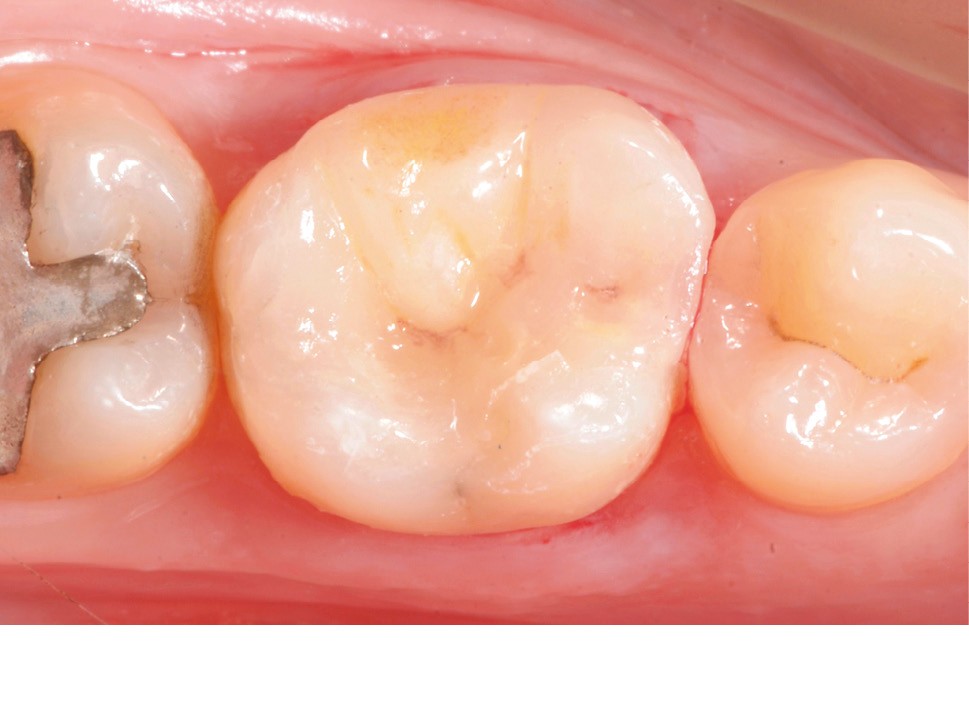

Lors de la préparation d’une cavité pour inlay/onlay, il est fréquent d’être confronté, en fin de nettoyage, à la présence d’une ou plusieurs parois résiduelles dont la résistance mécanique paraît douteuse du fait de leur localisation ou de leur épaisseur. Les parois épaisses (+ de 2 mm) peuvent généralement être conservées (cas clinique 1) et les parois fines (- de 1 mm) doivent généralement être recouvertes. Un inlay (en composite ou en céramique) est alors réalisé. Il doit avoir lui même, au final, une épaisseur globale minimale de 2 mm pour assurer sa résistance mécanique intrinsèque à la mastication. Si un recouvrement cuspidien est indiqué, la réduction occlusale doit donc se faire sur 2 mm de hauteur au minimum [1, 2].

Mais qu’en est-il des parois résiduelles d’épaisseur intermédiaire (entre 1 et 2 mm) (cas clinique 2) ?